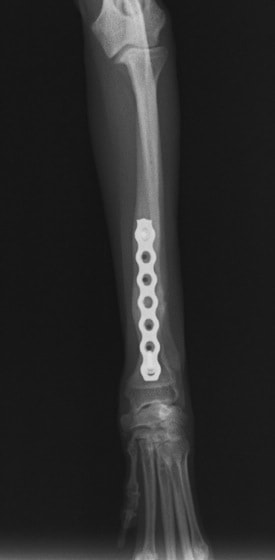

トイプードル 右遠位橈尺骨短斜骨折のALPSによる内固定

Locking Compression Plate

LCPは、スクリュー(ネジ)とプレート(金属の板)をロックする特殊な構造により骨折部位を固定する新しい世代のプレートシステムです。ひとつのホールでロッキングスクリューとスタンダードスクリューの使用を選択できるユニークな構造をしているため、骨折断端間の圧迫を目的とした従来型プレート固定法に加え、高い角度安定性を有するロッキングスクリューを用いた固定法の選択が可能です。従来のプレートシステムでは困難だった部分の骨折や癒合不全の症例に高い治療効果をもたらします。